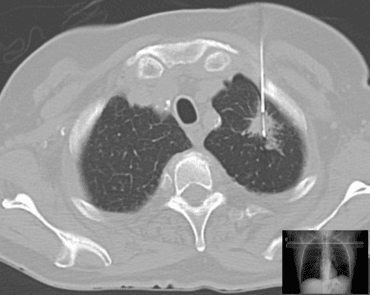

İnsan vücudunda gelişen birçok kitleye yönelik biyopsiler yapılabilir. En sık olarak karaciğer, pankreas, akciğer ve kemik gibi organlardan gelişen kitlelere yönelik tanısal tru-cut biyopsi işlemi yapılabilir. Bu biyopsi işlemlerinden akciğer kitlelerine yönelik biyopsi Bilgisayarlı tomografi eşliğinde yapılır.